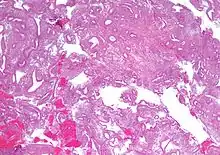

| Micrograph showing simple endometrial hyperplasia, where the gland-to-stroma ratio is preserved but the glands have an irregular shape and/or are dilated. Endometrial biopsy. H&E stain. | |

- Endometrial hyperplasia (simple or complex) - Irregularity and cystic expansion of glands (simple) or crowding and budding of glands (complex) without worrisome changes in the appearance of individual gland cells. In one study, 1.6% of patients diagnosed with these abnormalities eventually developed endometrial cancer.[6]